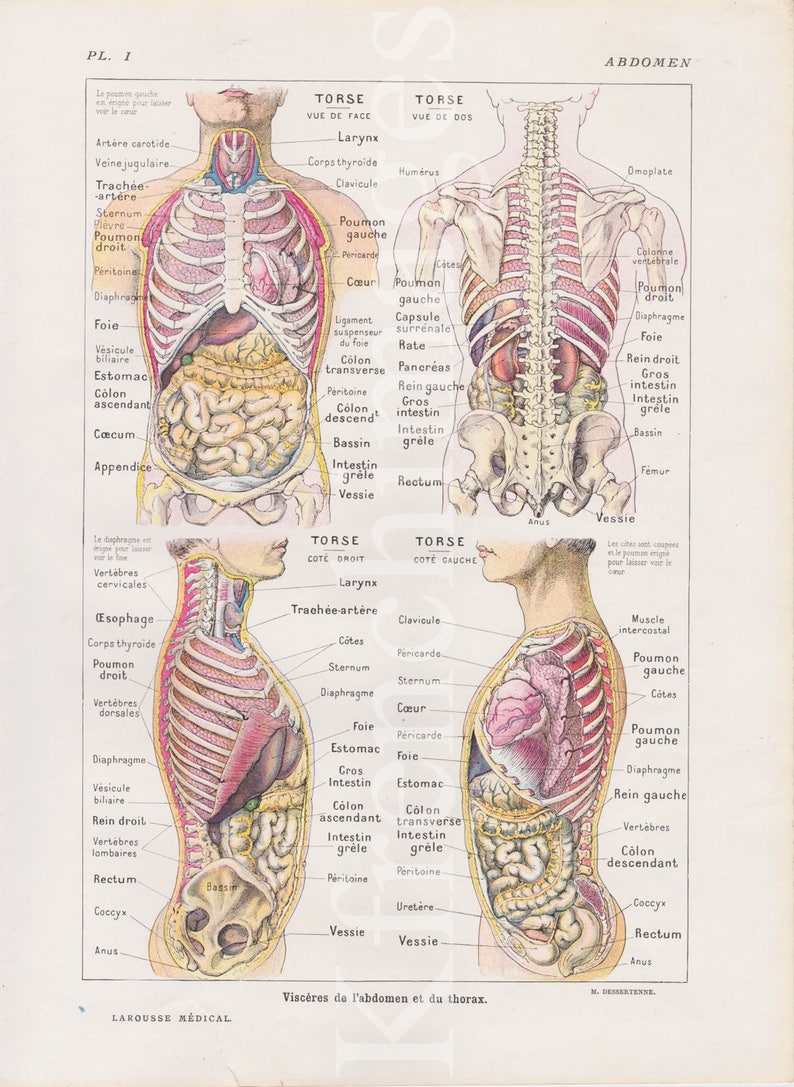

Torso Anatomy Plate French Vintage Original Print 1920's - Etsy  FIGURE PROCESS AND TORSO REF by HumanNature84 on DeviantArt | Figure sketching, Anatomy tutorial

Female Torso Anatomy Diagram : Vintage 1950's Frohse Chest & Abdomen Viscera Human  Pin on Drawing Guide